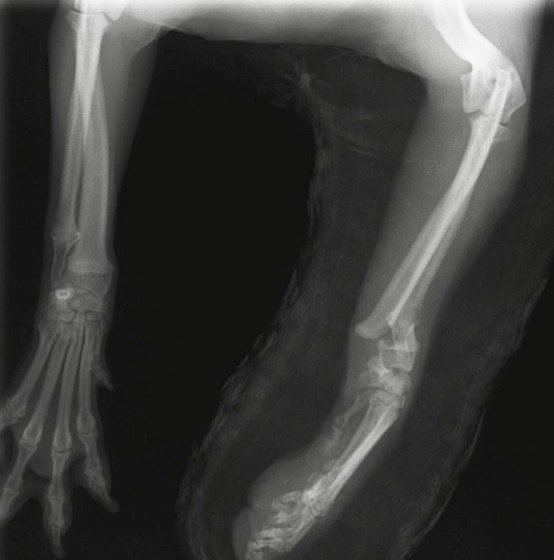

橈尺骨骨折 : 症例1 | 症例2 | 症例3 | 症例4 | 症例5 | 症例6 | 症例7

: 症例8 | 症例9 | 症例10 | 症例11 | 症例12 | 症例13 | 症例14

: 症例15 | 症例16 | 症例17 | 症例18 | 症例19 | 症例20 | 症例21